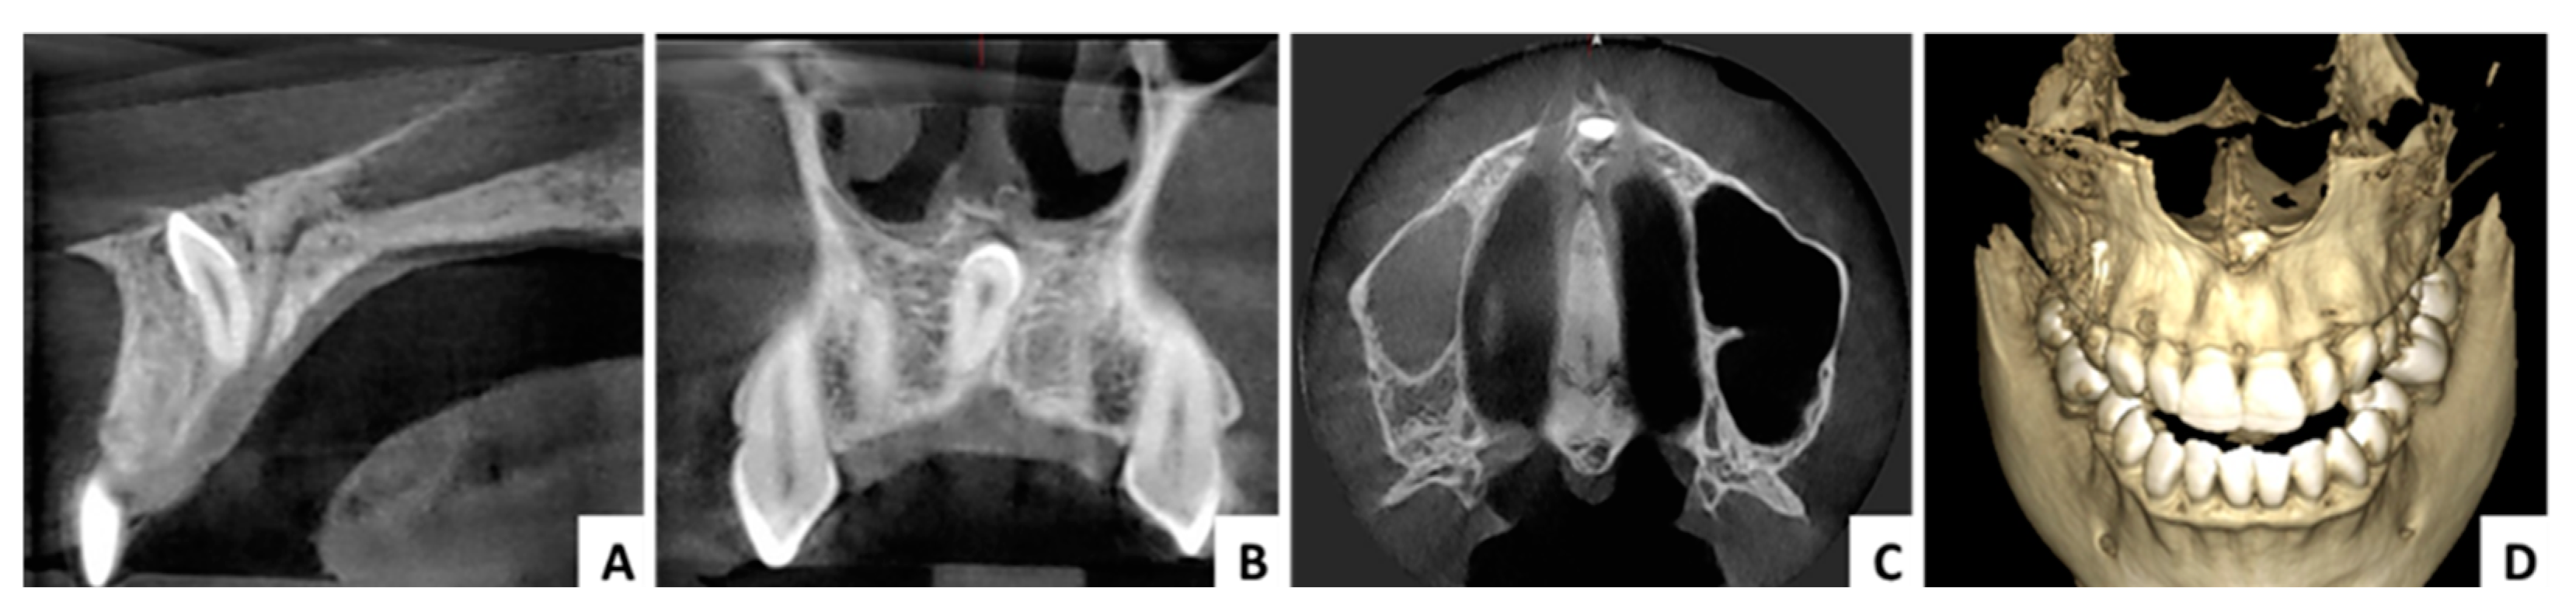

3.1. Case 1 (Figure 3, Figure 4 and Figure 5)